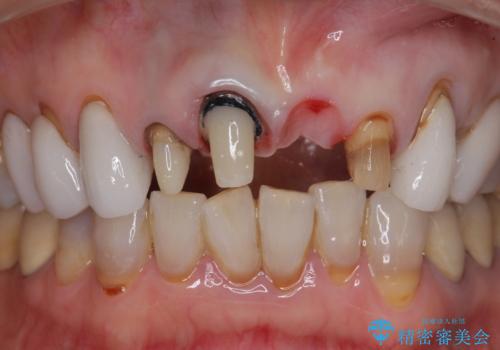

[ セラミック治療 ] 歯ぐきの際の黒ずみを改善したい

- 歯ぐきとセラミックの間の黒ずみが目立つので、きれいに治してほしい。と希望され来院されました。

歯ぐきの位置が変化しクラウン下の歯が見えるようになってしまったことで、審美障害が生じている状態です。

クラウンマージンの再設定を行うことで、黒ずんだ部分を再度覆い、審美障害を改善します。

- 52.8万円(ジルコニアクラウン×4・仮歯×4)費用は治療当時の料金となります